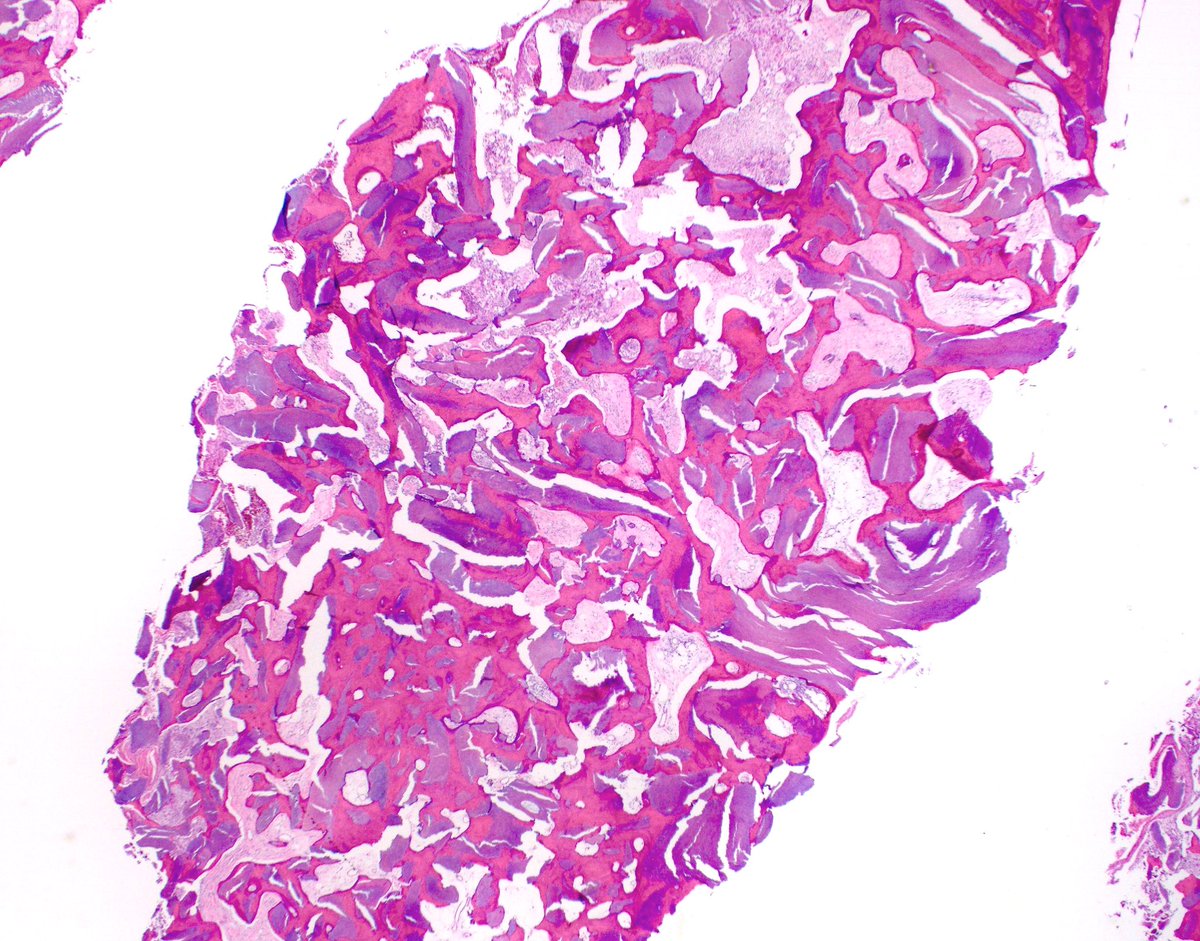

Striking example of the rare Mucinous Tubular Spindle cell carcinoma (MTSCC) of the kidney

#GUPath#GUPS#kidney#Cancer@UMichPath#pathologypic.twitter.com/UNwjNBPpW0